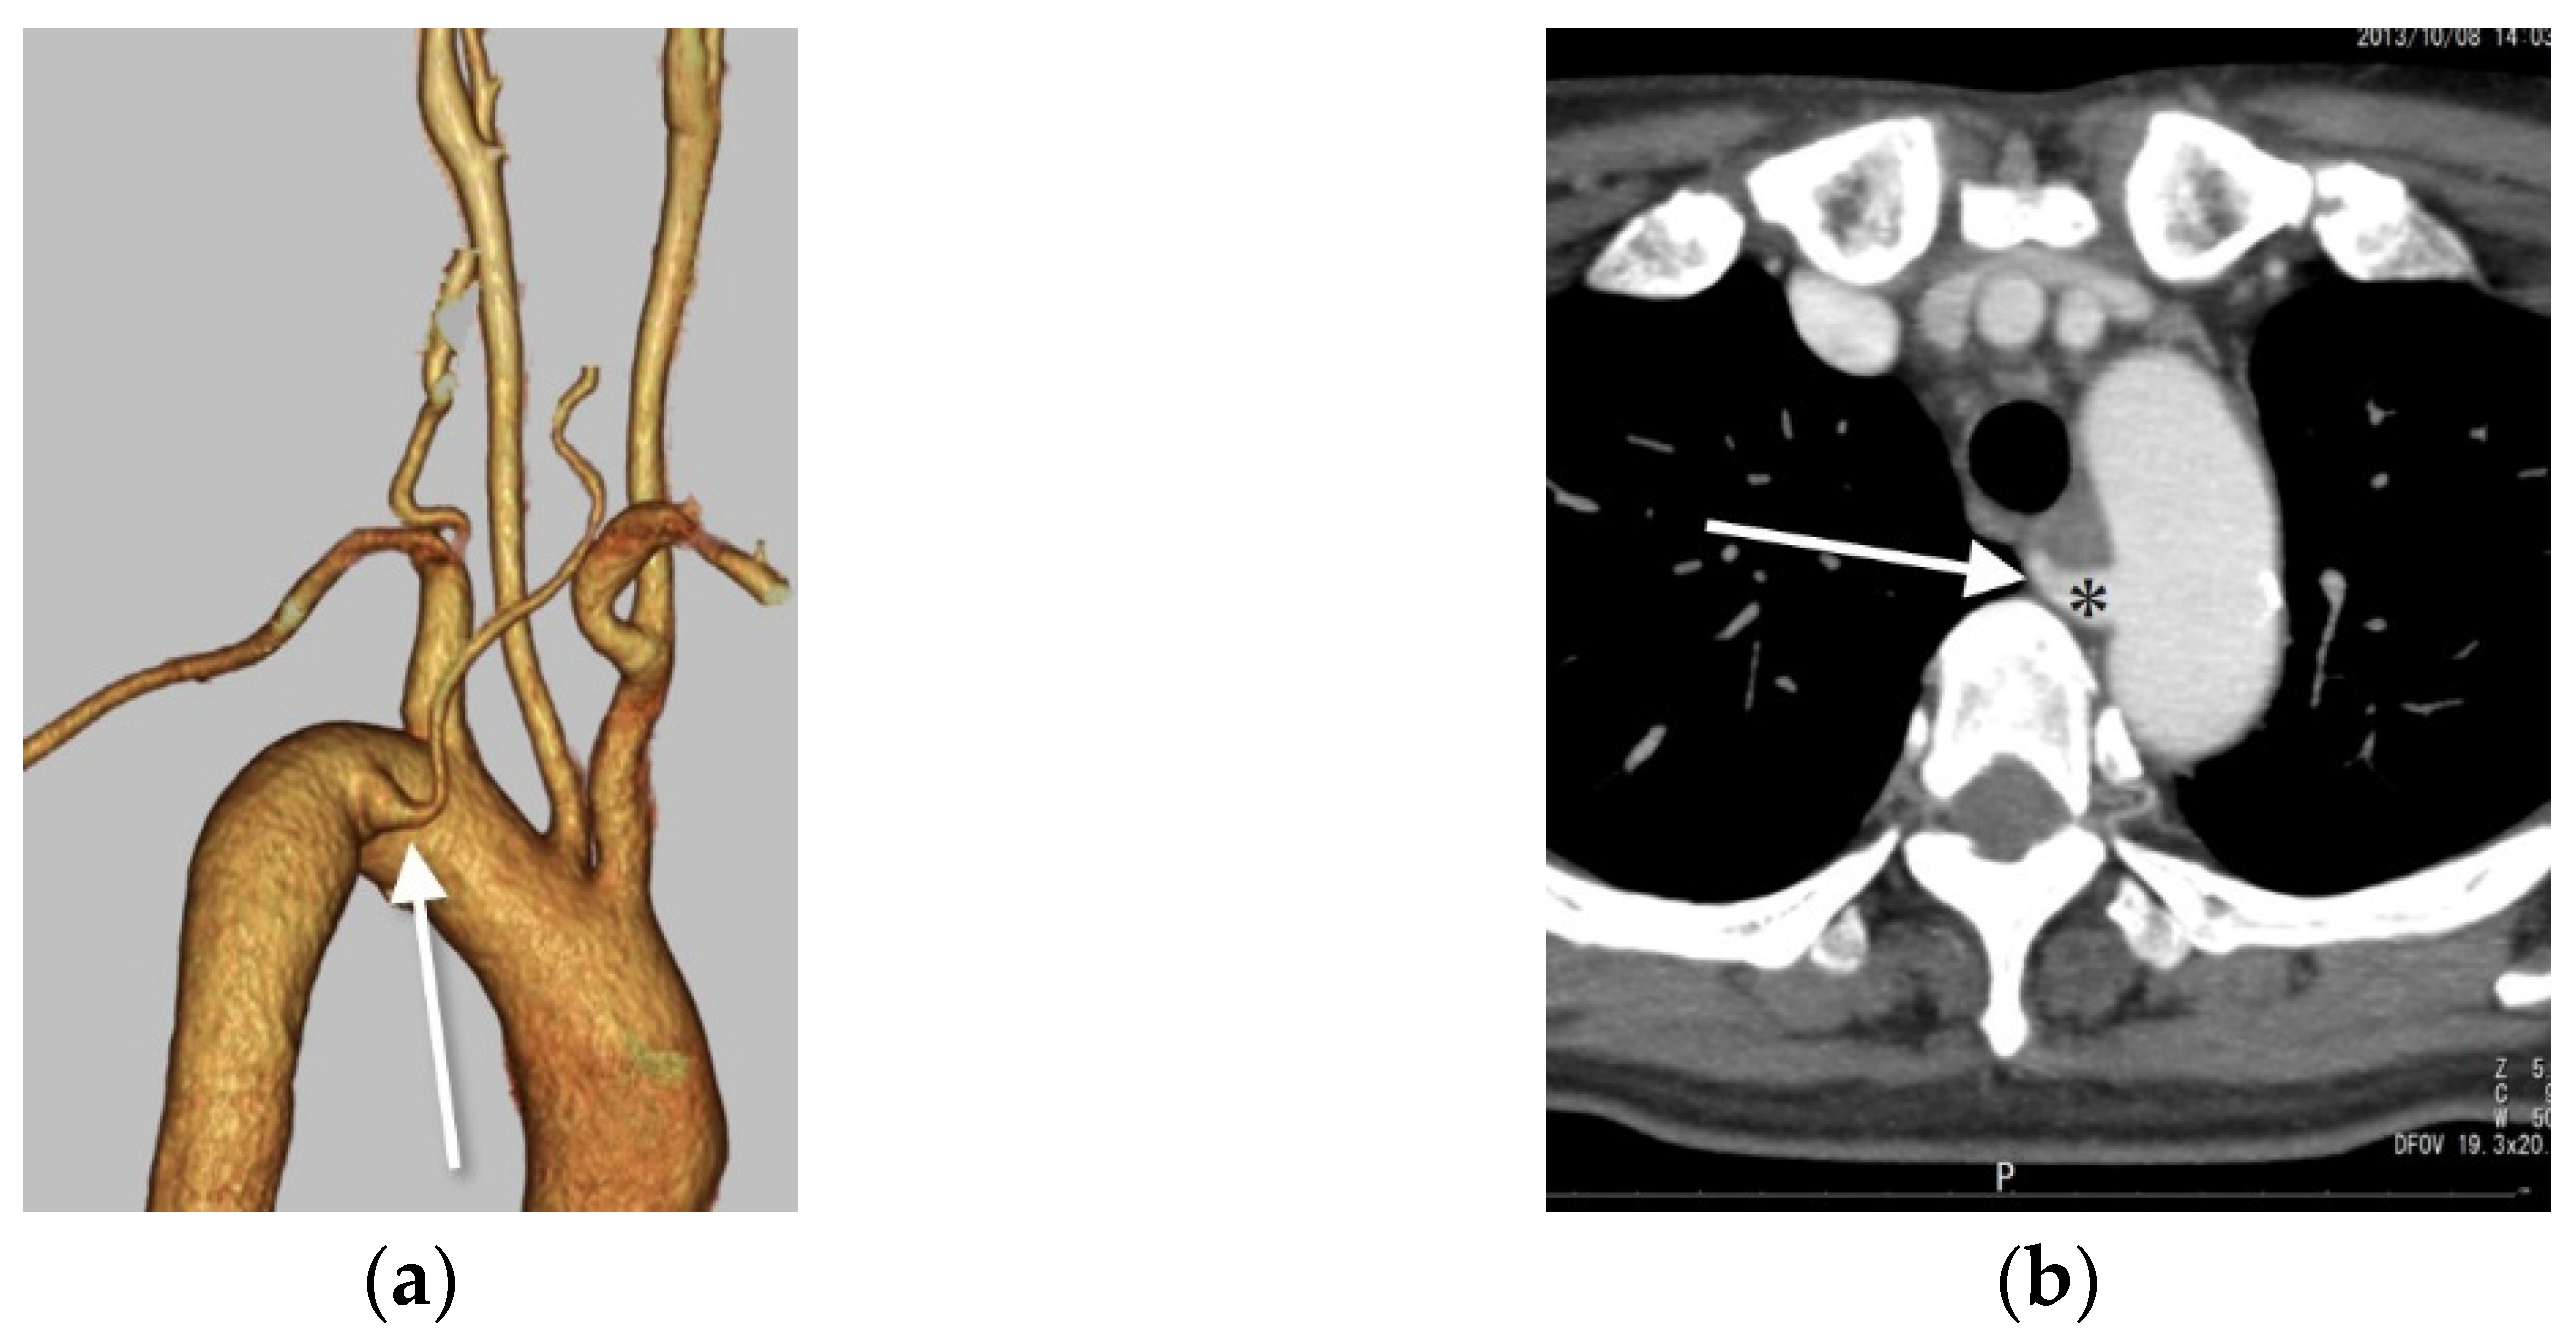

Figure 4.

Right VA originating from the aortic arch with a diverticulum of Kommerell. (a) Right posterior oblique view on VR-CT angiography shows the RVA directly arising from the aortic arch (long white arrow) distal to the left subclavian artery with a diverticulum of Kommerell. (b) Axial contrast-enhanced CT shows the right vertebral artery (white long arrow) arising from the aortic arch as the fourth branch with a diverticulum of Kommerell (*). The Ziostation 2 (Ziosoft Inc., Tokyo, Japan) was used to obtain the VR image.